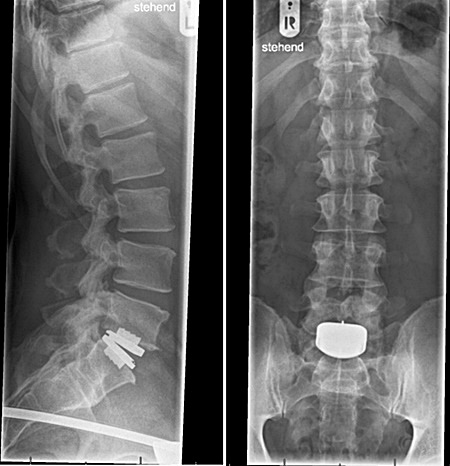

After being ruled

inoperable, my wife and I

traveled to Germany, where

in

May of 2014, I had a

Pro-Disc ADR implanted at my

damaged L5-S1 area, as

illustrated on the right.